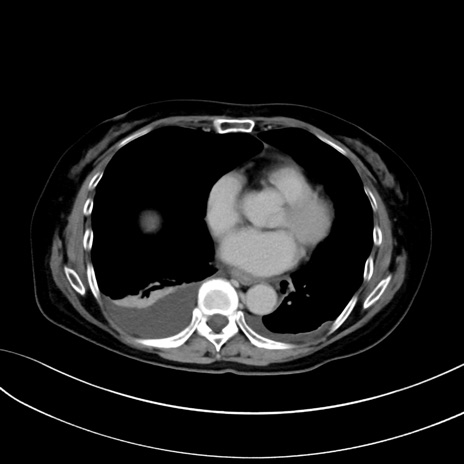

症例13 CT(横断像)1日半後